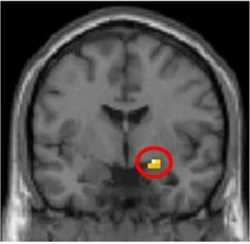

V časopise Public Library of Science Biology to oznámil šesťčlenný tím Katariny Gospicovej z Karolínskeho inštitútu v Štokholme a Erika Mohlina z University College v Londýne. Zdrojom tejto reakcie je amygdala, párová štruktúra hlboko v strednej časti spánkových lalokov mozgovej kôry, jedna z evolučne starších častí mozgu. Vyplynulo to z pokusnej peňažnej hry vždy dvoch subjektov, ktorým vedci sledovali mozgovú činnosť zobrazovaním pomocou magnetickej rezonancie. Hra sa zakladá na univerzálnom ľudskom správaní: agresívnej reakcii, ak iná osoba poruší nefér konaním normu správania, ktorá je v najlepšom záujme celej skupiny.

Mozgový skener odhalil, že predmetné finančné rozhodnutia ovláda amygdala, evolučne stará a teda primitívnejšia časť mozgu, ktorá sa podieľa aj na pocitoch hnevu a strachu. Skoršie výskumy naznačovali, že schopnosť analyzovať a rozhodovať o finančných otázkach sídli výlučne v prednej časti čelového laloka mozgovej kôry. Vedci hráčom podali buď sedatívum Oxazepam, ktoré sa predpisuje proti úzkosti, alebo placebo. Zistili, že hráči, ktorí dostali liek, mali menej aktívnu amygdalu a boli náchylnejší prijať nefér rozdelenie peňazí, hoci ho – keď sa ich vedci na to priamo spýtali – stále posudzovali ako nefér.